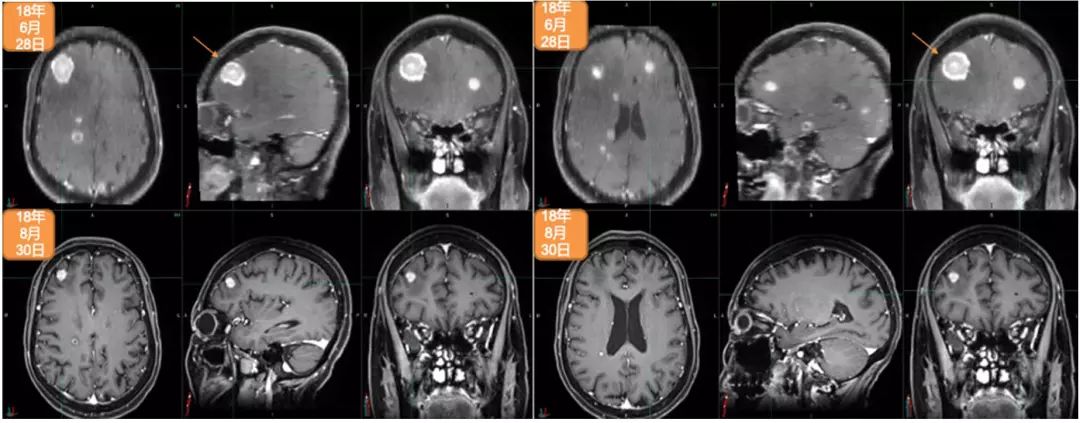

2018年5月,出现全身状况下降。2018年6月28日,进行脑部MRI检查:多发脑转移,右额叶最大病灶达2.5cm。2018年7月4日,进行PET/CT检查:多发纵隔淋巴结、胸腔和骨转移。2018年7月5日,进行右髂骨活检:转移性腺癌,原发于乳腺(BRST2+),ER-,PR-,HER2++,FISH+,Ki67:20%。

2018年7月12日至2018年7月25日期间,进行姑息性海马保护性全脑照射:30Gy,10次分割 。2018年6月15日开始姑息性TDM-1(Kadcyla®)200mg治疗。2018年12月7日,进行第8个周期治疗。2018年8月30日,进行脑部MRI检查:疾病缓解,右额叶最大病灶缩小至1.12cm。2018年8月31日,进行PET/CT检查:疾病缓解,包括胸腔积液缓解、肺原发灶、淋巴结和骨转移灶缩小并被吸收。治疗过程中仅有轻度不适,未出现显著的骨髓抑制或肝炎。Hb:11.1–12.2g/L;WBC:3.01–3.57×109/L;血小板:69-79(G2)。2018年12月28日开始下一个周期治疗。

2018年6月28日与2018年8月30日头颅MRI对比